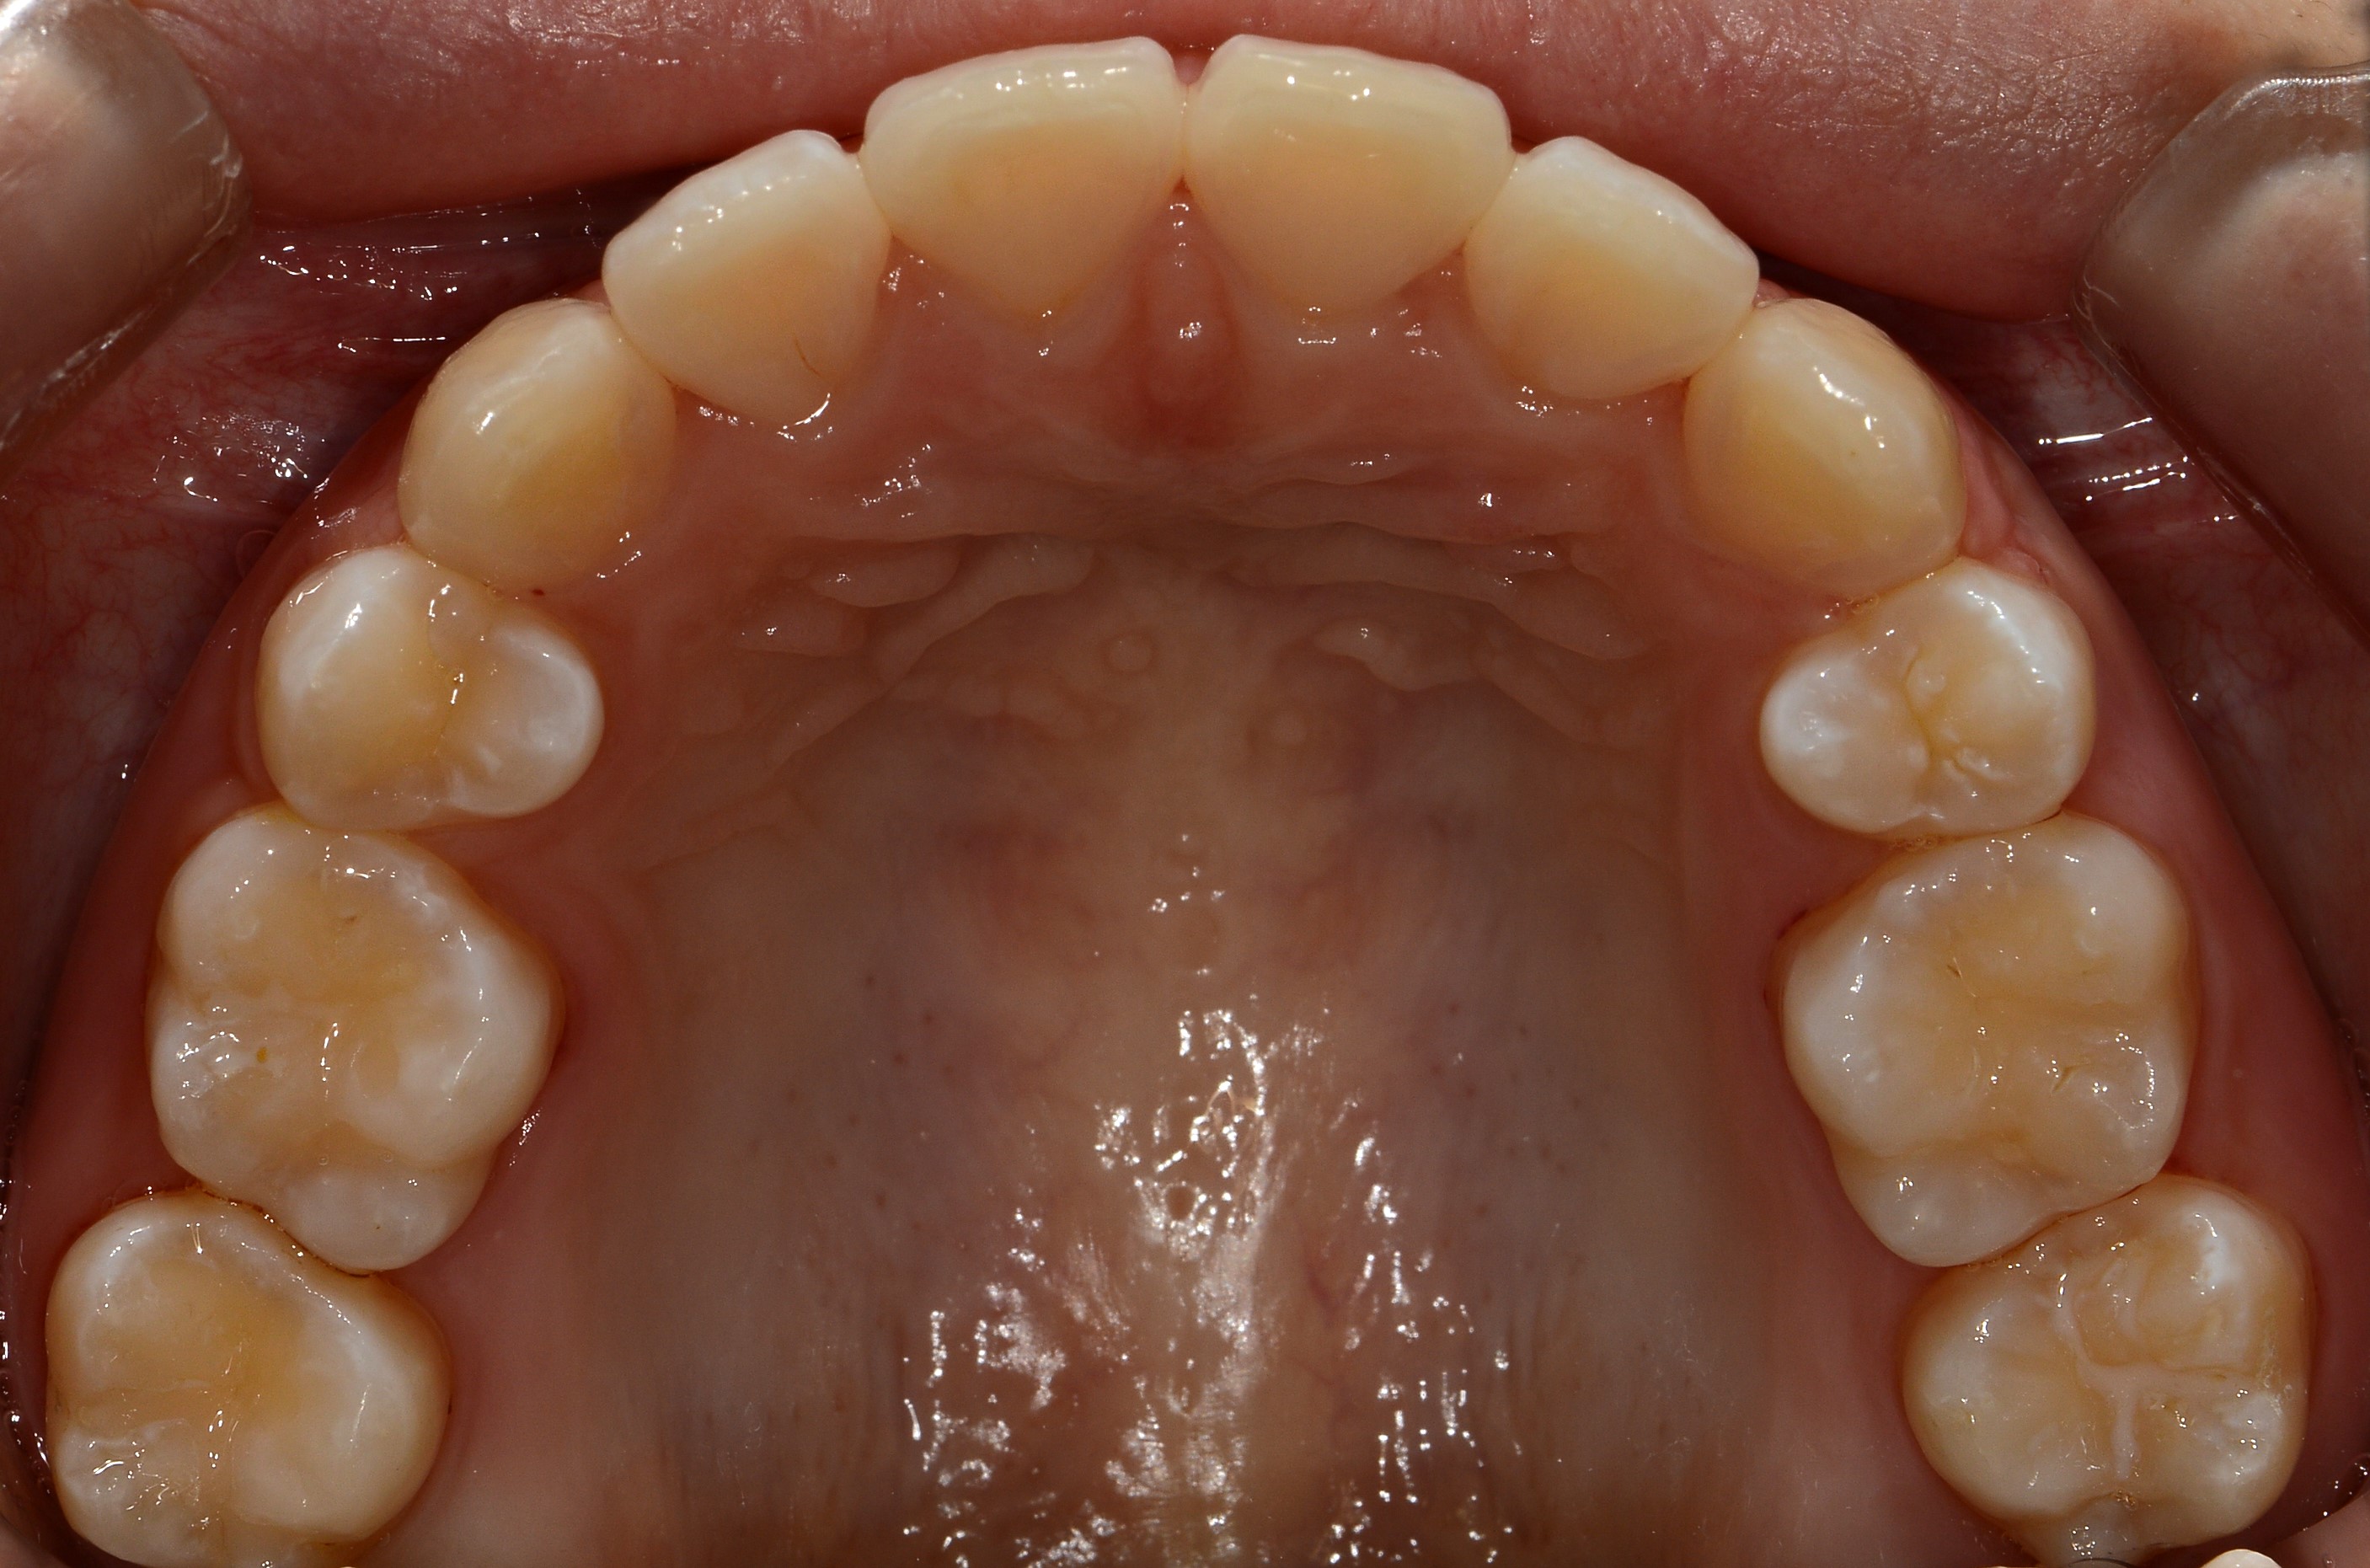

치료 전 사진입니다.